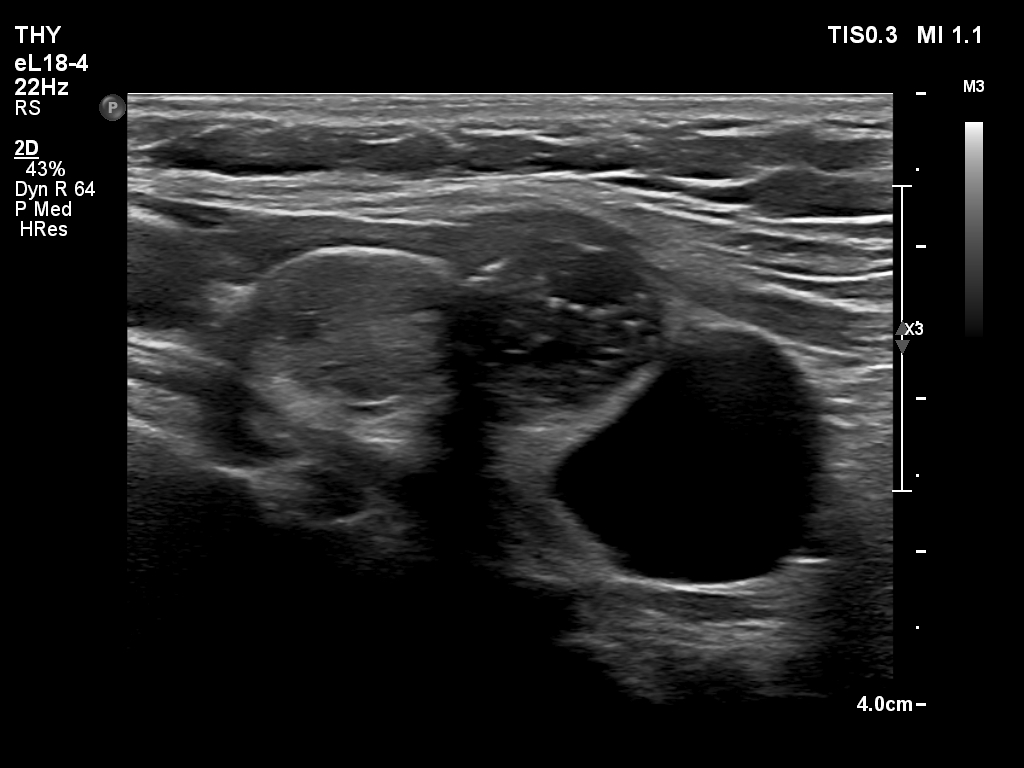

Ultrasonography. The thyroid was echonormal and had multiple nodules. There were cystic areas, an almost completely cystic nodule, and a dominantly solid nodule in the right lobe. The left lobe had three lesions. The upper solid lesion was the one we treated 16 years ago. The middle lesion was a dominantly solid while the lower one seemed to be a pure cyst. The dimensions of the nodule which has been treated with sclerotherapy were 10x11x13 mm (width, depth and length, respectively). There was a large cystic nodule in the upper pole of the left lobe. The lesion showed relatively large hyperechogenic granules. There were multiple enlarged lymph nodes lateral to the left lobe, two of largest were cystic.

After removing 4 mL fluid from the lowest lesion in the left lobe, the lesion has disappeared, which proves that this was a pure cyst. Cytology resulted in cystic degeneration.